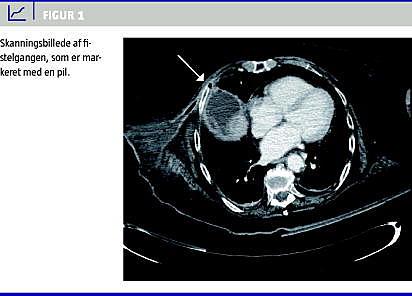

Seks uger senere blev patienten genindlagt med tegn på absces i højre mamma. Man fandt rødme og induration af papillen og den nedre laterale kvadrant af højre bryst strækkende sig om på ryggen. Abscessen blev incideret under udtømning af pus og galde. En computertomografi (CT) afslørede, at den subfreniske ansamling var gendannet, og at der via interkostalrum 4 var forbindelse til mammaabscessen (Figur 1 ). Patienten blev behandlet med en ny UL-vejledt drænage af den subfreniske ansamling samt ERCP med papillotomi og internt dræn. Sekretionen af galde fra såret på mamma ophørte, men den subfreniske absces gendannedes, hvorfor der blev foretaget åben kolecystektomi. Galdeblæren var skrumpet og dybt indlejret i leveren, men uden relation til det subfreniske rum, hvorfor transhepatisk perforation af højre leverlaps overflade ikke kan udelukkes.

Årsagen til den her omtalte sjældne fistulering er formentlig, at den subfreniske absces har løftet diafragma på højre side og derved skabt mulighed for en fistel til mamma (Figur 1).

Udredning omfatter UL- og MR-skanning, CT samt fistulografi. De tre sidstnævnte modaliteter er velegnede til identifikation af abscesser, fistelgange og anden patologi. I denne sygehistorie blev der ikke foretaget fistulografi, men en CT viste fistelgang fra den subfreniske ansamling til mamma.